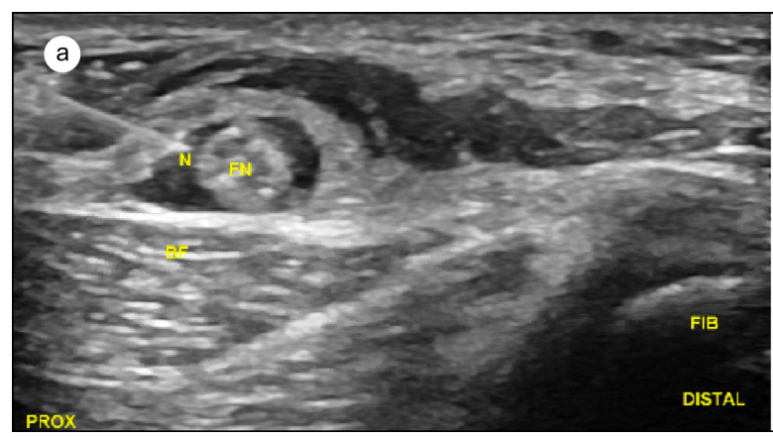

이때 활약한 것이 바로 '정밀 초음파'입니다.

초음파로 신경을 직접 들여다보니,

신경 섬유 내부가 부어있는 것이 확인되었죠.

그런데 시술하다보면

염증으로 들러 붙은 유착 부위나

상처가 나서 딱딱하게 섬유화된 흉터에는

약물이 잘 들어가지 않습니다.

이런 모습을 보면서

MRI에서 나타나지 않던

신경의 압박 부위를 확인할 수 있는 것이죠.